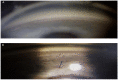

Ocular trauma affects millions of people worldwide and is a leading cause of secondary glaucoma. Angle recession is the main cause of post-traumatic glaucoma after blunt eye trauma, and it is usually unilateral. The aim of this paper is to investigate the possible causes of angle recession with a bilateral presentation. Airbag activation during traffic accidents is a likely cause to be ruled out, along with repeated head or eye trauma, due to contact sports or a history of physical abuse. These aspects can aid in early detection, appropriate management, and improved outcomes for patients with ocular trauma. Finally, we report the case of a 75-year-old Caucasian man who developed a bilateral angle recession after an airbag impact, with advanced glaucoma in the right eye and ocular hypertension in the left eye. To our knowledge, this is the first case in the literature of chronic post-traumatic glaucoma probably caused by an airbag.